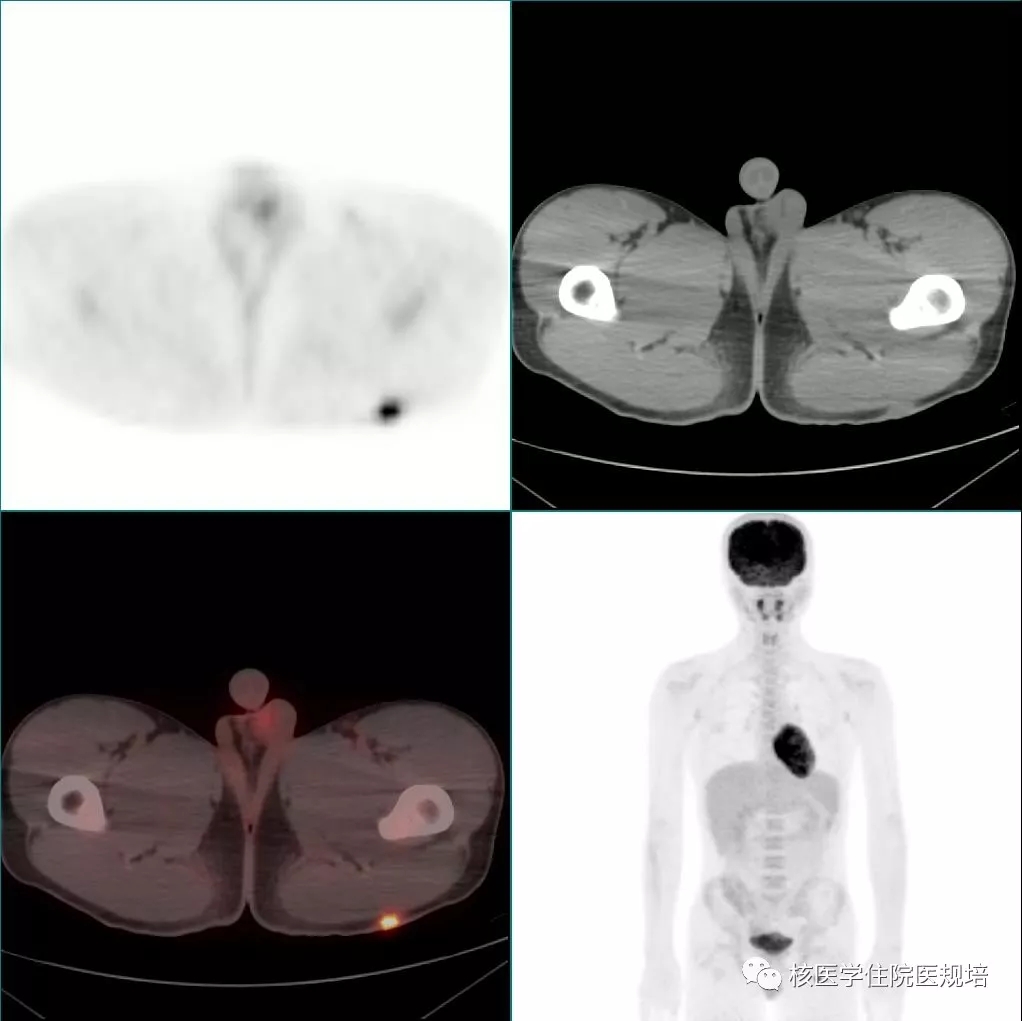

18F-FDG PET/CT显像见:左室前侧壁显影形态失常,MR所示占位相应部位与周围正常心肌组织对比呈不均匀FDG摄取减低区(SUVmax6.4),但肿物边界观察不清,相当于乳头肌处见点状FDG高摄取(图4);双侧腋窝区域分别可见一FDG摄取轻度增高(SUVmax1.8)的小淋巴结,对称性分布,淋巴结均呈长椭圆形,短径均小于1.0cm,内可见脂肪密度的门样结构(图5);另于左侧臀部下方皮下脂肪层内可见一点状FDG摄取增高灶(SUVmax6.1),相应部位CT见一边界较清晰的软组织密度结节影(图6,追问病史该结节已存在3年,局部无红肿热痛,大小始终无著变。全身其余部位未见明显异常结构改变及FDG摄取。

图5

图6